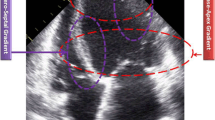

The LVNC patients were divided into two groups based on QTc interval: normal QTc group (QTc ≤ 440 ms, n = 18), and prolonged QTc group (QTc > 440 ms, n = 14). The typical LVNC imaging was shown in the Fig. 1. The healthy volunteers showed normal electrocardiogram. Table 1 shows the baseline characteristics of patients and healthy controls. There were no significant differences in age, or body mass index among patients with normal QTc, patients with prolonged QTc, and the healthy controls. Family history of LVNC was found in seven patients in the normal QTc group and two patients in the prolonged QTc group.

The CMR imaging data are presented in Table 2. The mean T1 values in the healthy controls and LVNC patients (patients with prolonged QTc and patients with normal QTc) were 1096.0 ± 41.5 and 1159.1 ± 47.4 ms, respectively. The mean T1 values in patients with normal QTc and patients with prolonged QTc were 1141.98 ± 45.46 and 1182.67 ± 42.02 ms, respectively (Fig. 2). One-way ANOVA showed significant differences in native T1 among three groups (F = 14.9, p < 0.001) while Post Hoc Student–Newman–Keuls analysis showed significant differences in native T1 values between any two groups. No significant differences were observed in the thickness of compacted myocardium and the NC: C ratio between normal QTc and prolonged QTc group.

After adjusting for body surface area, one-way ANOVA showed significant differences in LV mass, LV end-systolic volume (LVESV), and LV end-diastolic volume (LVEDV) among the three groups (F = 10.8, p < 0.001; F = 17.5, p < 0.001; F = 13.2, p < 0.001; respectively). The post-hoc with Student–Newman–Keuls analysis showed significant differences in LV mass, LVESV, and LVEDV among three groups, but no significant differences were observed between all patients and healthy controls (Table 3). There was no difference in non-compaction segments between normal QTc and prolonged QTc group (p = 0.79). The distribution of non-compaction segments of the two groups are shown in the Fig. 3.

Distribution of non-compaction (NC) segments. a Normal QTc LVNC patient. b Prolonged QTc LVNC patient. The heart was divided into 17 segments according to AHA standard segments. The number in each segment shows the total NC segments. For example, at the apical, a and b pictures have seven and ten subjects with NC segments, respectively